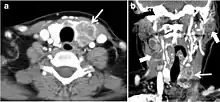

Fig. 6. A 61-year-old female patient with locally aggressive PTC. an Enhanced axial CT scan of the neck demonstrates a heterogeneous infiltrative thyroid mass. This mass diffusely involves the entire gland and circumferentially encases the trachea with involvement of bilateral tracheoesophageal grooves (white arrows). b, c Additional axial cranial images show right cricoid cartilage destruction (black arrows in b), right thyroid cartilage destruction (black arrow in c), right vocal cord paralysis (white arrows in b), and bilateral cervical lymphadenopathy (arrowheads).[1]